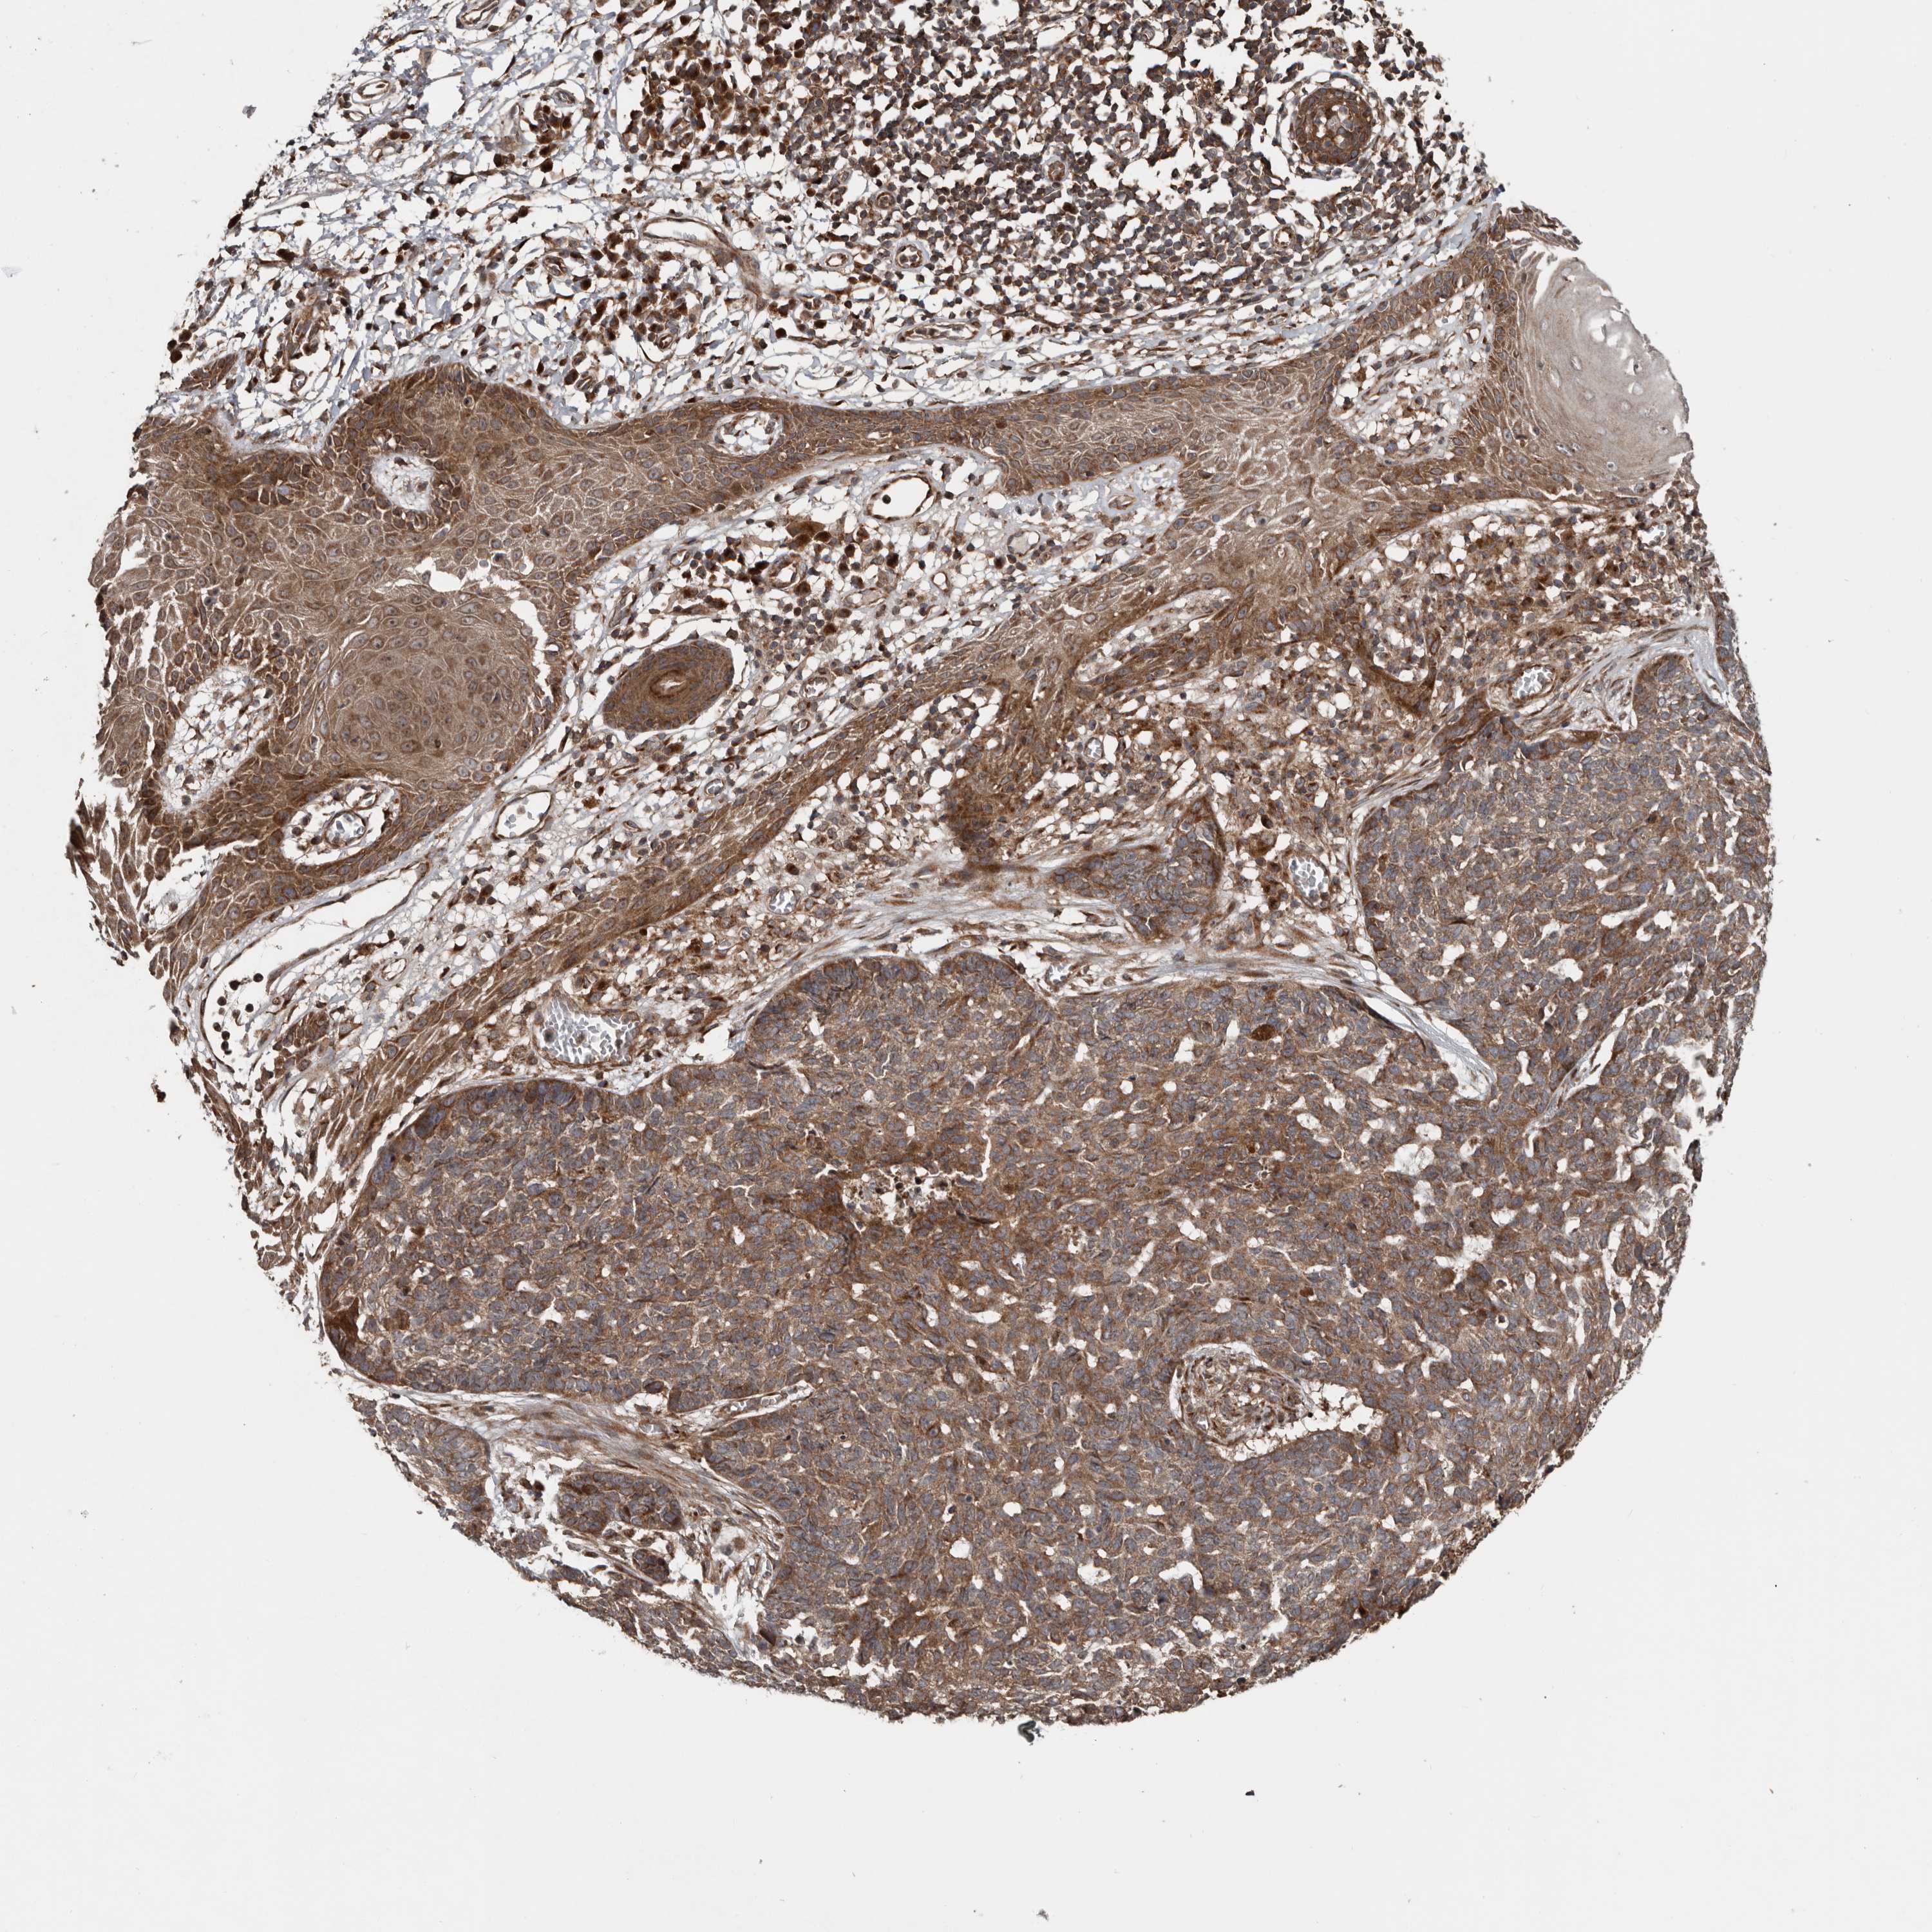

SKIN CANCER - Protein expressioni

A mouse-over function shows sample information and annotation data. Click on an image to view it in a full screen mode. Samples can be filtered based on level of antibody staining by selecting one or several of the following categories: high, medium, low and not detected. The assay and annotation is described here.

Each image is clickable and will lead to virtual microscopy that enables deeper exploration of all samples and also displays staining intensity scores, fraction scores and subcellular localization as well as patient and tissue information for each sample.

Antibody HPA028579

Staining

High

Medium

Low

Not detected

Intensity

Strong

Moderate

Weak

Negative

Quantity

>75%

75%-25%

<25%

None

Location

Nuclear

Cytoplasmic/membranous

Cytoplasmic/membranous,nuclear

Basal cell carcinoma